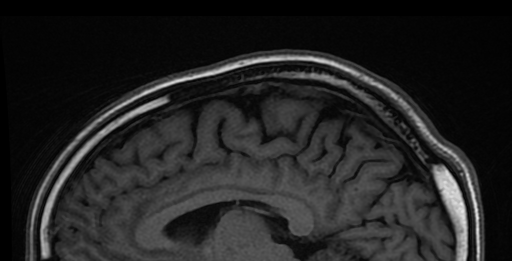

Аппарат МРТ мощностью 11.7 Тесла проекта Iseult сделал замечательные анатомические изображения живых существ. человек мозг участников. Это первое исследование вживую человек мозг с помощью аппарата МРТ с такой высокой напряженностью магнитного поля, который позволил получить изображения с разрешением в плоскости 0.2 мм и толщиной среза 1 мм (что соответствует объему, эквивалентному нескольким тысячам нейронов) за короткое время сбора данных, всего 4 минуты.

Изображение человек мозг с этим беспрецедентным разрешением с помощью аппарата Iseult MRI позволит исследователи раскрыть новые структурные и функциональные детали человек мозг которые могут пролить свет на то, как мозг кодирует мысленные представления или что такое нейронные сигнатуры сознания. Новые открытия могут помочь в диагностике и лечении нейродегенеративных заболеваний, таких как болезнь Альцгеймера и Паркинсона. Эта машина также может помочь в обнаружении химических веществ, участвующих в метаболизме мозга, которые иначе не могут быть обнаружены с помощью МРТ-аппаратов с более низкой напряженностью магнитного поля.

Этот МРТ-сканер с мощностью 11.7 Тесла проекта Iseult является самым мощным в мире. человек аппарат МРТ всего тела, установленный в NeuroSpin в CEA-Париж-Сакле. Первые изображения были предоставлены в 2021 году, когда они отсканировали тыкву и предоставили изображения с разрешением 400 микрон в трех измерениях, что подтвердило эффективность процесса.